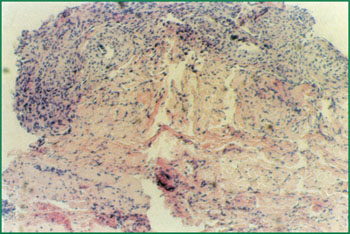

1¡¢ ¢ó¶ÈÉÕÉËÕ¼×ÜÃæ»ý85%µÄ²¡ÈË£¬£¬£¬£¬£¬ÓÒ²àΪƤ·ôÈ«²ã»µËÀ£¨²¡ÀíÇÐÆ¬£©¡£¡£¡£ ¡£ ¡£¡£¡£¡£

4¡¢ ÉÕÉË»µËÀƤ·ôÒº»¯É¨³ý´´ÃæÐγÉÏËά¸ôÀëĤ£¬£¬£¬£¬£¬ÐÂÉúµÄƤ·ô×éÖ¯ÔÙÉú»Ø¸´´´Ã棨²¡ÀíÇÐÆ¬£©£¬£¬£¬£¬£¬(É˺óµÚ20Ìì)¡£¡£¡£ ¡£ ¡£¡£¡£¡£

5¡¢ ÉÕÉË´´ÃæÔÚMEBOºÍÏËά¸ôÀëĤµÄ±£»£»£»£»£»£»¤Ï£¬£¬£¬£¬£¬ÔÙÉúµÄƤ·ô×éÖ¯ÐγÉ÷缯µÄƤµº(É˺ó25Ì죩¡£¡£¡£ ¡£ ¡£¡£¡£¡£

6¡¢ ²¡ÀíÇÐÆ¬£ºÔ­Î»¸Éϸ°ûÔÙÉú»Ø¸´Æ¤·ô¡£¡£¡£ ¡£ ¡£¡£¡£¡£

8¡¢ ÒÑÓúºÏµÄƤ·ô×éÖ¯ÇÐÆ¬£¬£¬£¬£¬£¬¿É¼ûÒÑÐγÉÕý³£µÄƤ·ô×éÖ¯½á¹¹¡£¡£¡£ ¡£ ¡£¡£¡£¡£(É˺ó49Ì죩¡£¡£¡£ ¡£ ¡£¡£¡£¡£

9¡¢ É˺óµÚ72Ì죬£¬£¬£¬£¬´´ÃæÆ¤·ôÈ«²ãÔÙÉú»Ø¸´ÓúºÏ¡£¡£¡£ ¡£ ¡£¡£¡£¡£